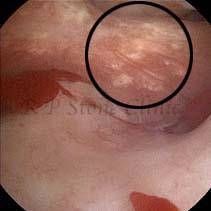

Kidney stone is a solid mass of CRYSTALS. It is the process of crystallization which initiates the formation of kidney stones. This happens in nephrons or units of kidney. Once a small crystal is formed, it can both grow & unite with other crystals leading to the formation of small concretion which eventually forms a stone. Once these large crystals detach from the collecting ducts, the process of stone formation starts in the renal collecting system. A recurrent kidney stone former is advised to know a little bit about something known as Randall’s plaque. Alexander Randall discovered plaques on the renal papillae eight decades back based on examination of 1154 pairs of autopsied Kidneys. He described these renal papillary lesions as cream colored or milk patch areas composed of calcium phosphate & calcium carbonate. These plaques could act as NIDUS for formation of KIDNEY STONE. Calcium Oxalate stone can form on this nidus & then detaches from this plaque to become a free floating stone in the collecting system of kidney

These images are taken as snap shots from the video recording of RIRS Surgery done at our hospital. These are Randall’s Plaques seen with Digital FLEX XC & Digital FLEX XC S. The cream or whitish patches are seen on the tips of RENAL PAPILLAE as seen in images below.

Randall’s Plaques may lead to the formation of Stones.

Those kidney stone patients who have Randall’s Plaques in their kidneys are more likely to form stones again (Recurrent Stones).

Stone Patients in whom Randall’s Plaques are detected at the time of RIRS Surgery should undergo regular ultrasound examination for early detection of stones.

Patients of Stones with Randall’s Plaques in their Kidneys should drink plenty of fluids in addition to Orange Juice & Lemonade.